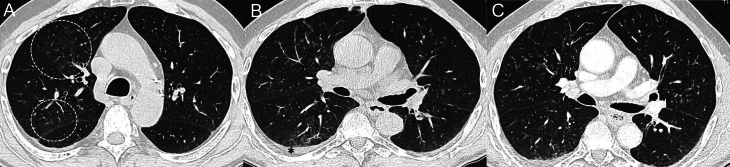

高选择性RET抑制剂赛帕替尼对晚期/进展期RET突变甲状腺髓样癌(MTC)患者有显著疗效。然而,尽管该药的毒性比多激酶抑制剂更易耐受,但也出现了一些特殊的不良事件(AEs)。闭塞性细支气管炎(OB)是一种以小传导气道炎症和纤维化为特征的呼吸系统疾病。我们对一名70岁的晚期RET突变MTC患者进行了评估,该患者在接受赛帕替尼治疗期间出现了阻塞性支气管炎。OB的放射学特征出现较早,并在赛乐替尼治疗期间持续存在,呈消长模式。值得注意的是,在治疗期间,MTC 获得了部分应答,而舍培卡替尼从未减量或中断。OB几乎完全没有症状,而且呈波动趋势,没有针对OB的特殊治疗,这表明有必要仔细评估这种AE介导的风险以及修改或中断抗癌疗法的风险。

Highly selective RET inhibitor selpercatinib has demonstrated notable efficacy in advanced/progressive RET-mutant medullary thyroid cancer (MTC) patients. However, despite a more tolerable toxicity profile than multikinase inhibitors, peculiar adverse events (AEs) have been described. Obliterative bronchiolitis (OB) is a respiratory disease characterized by inflammation and fibrosis in small conducting airways. We evaluated a 70-year-old man with advanced RET-mutant MTC who developed OB during treatment with selpercatinib. Radiological features of OB occurred early and persisted during selpercatinib treatment, with a waxing and waning pattern. Notably, a partial response of MTC was achieved during the treatment, and selpercatinib was never reduced or interrupted. The almost complete absence of symptoms and the fluctuating trend, without specific treatment for OB, suggested that it is necessary to carefully evaluate the risks mediated by this AE with the risks of modifying or discontinuing the anti-cancer therapy.